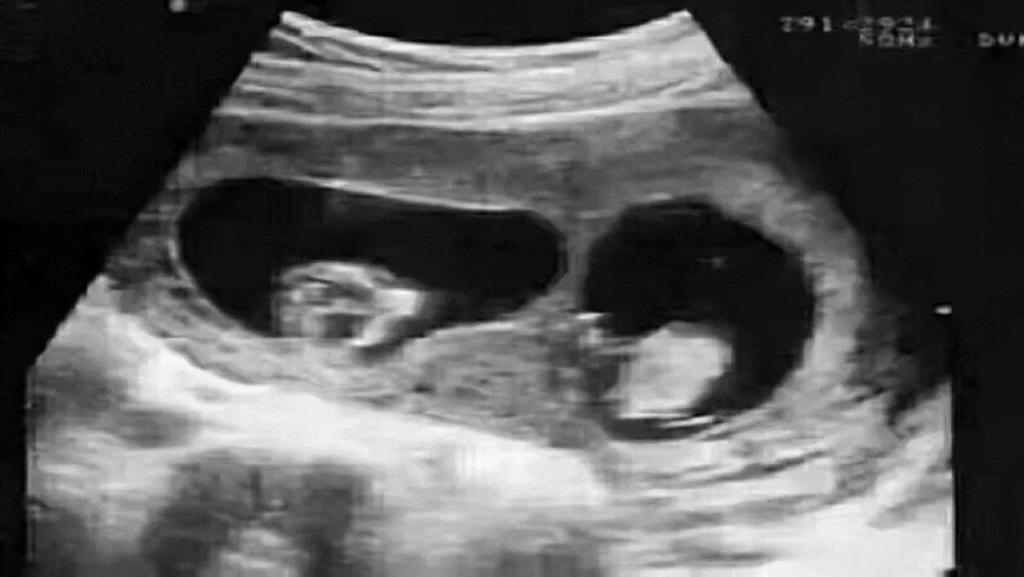

广医三院法医物证司鉴所马晓燕:这可能就遇到了鉴定行业中非常罕见的嵌合体案例,也就是说,这位“爸爸”身体内携带有两个人的 DNA,可能他在妈妈肚子里的时候,还有一个双胞胎弟弟,但是这个双胞胎弟弟的胚胎没有发育下来,反而和他的胚胎出现了融合,导致这个“爸爸”携带两个人的 DNA 出生,而且他把弟弟的 DNA 传给了孩子。

嵌合体其实也称为“奇美拉”现象。奇美拉原本指的是希腊神话中,一种狮头,羊身蛇尾的怪物,可以参考中国的四不像。而嵌合体正是一个人的体内含有多组 DNA 的现象,也可以通俗的理解为两个受精卵融合成一颗的现象。科学家认为这个发作概率大概在 10%-15%。

第一种就是和上文的事例一样,属于双胞胎在发育过程中,另一个抢不过对方,从而导致被“吞噬融合”,只能留下一部分 DNA 了。不过这也不要觉得残忍,算是生命的一种优胜劣汰吧,毕竟双胞胎原本对营养、空间等方面有更多需求,属于是无意识的行为吧,当然这是比较少见的情况。毕竟全世界这种被报道出来的,不超过 100 例。